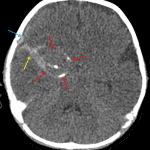

Age: 2 months

Sex: Female

Indication: Fussiness, bulging anterior fontanelle

CT

Giant cerebral aneurysm